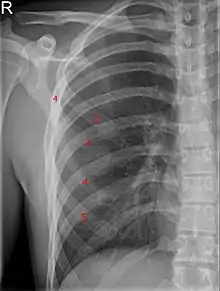

| Bifid rib at the right side seen on chest radiograph. The fourth rib splits in two towards the sternal end. | |

A bifid rib is a congenital abnormality of the rib cage and associated muscles and nerves which occurs in about 1.2% of humans. Bifid ribs occur in up to 8.4% of Samoans.[1] The sternal end of the rib is cleaved into two. It is usually unilateral.[2]